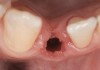

Fig 34. A surgical cover screw was placed in an attempt to decoronate the implant and gain soft-tissue coverage in situ.

Fig 35. A transitional resin-bonded-retained (RBR) bridge that was tooth supported was placed to allow soft-tissue maturation.

Fig 36. Two weeks after RBR placement, the soft tissue did not adequately cover the implant. The problem was in poor implant angulation and proper depth to allow the soft tissues to cover over.

The crown and screw-retained custom abutment were removed, and a surgical cover screw was placed into the implant, thereby allowing spontaneous gingival augmentation in situ (Figure 33 and Figure 34). Note that the lingual aspect of the implant site was significantly more coronal than the labial aspect, which was positive because the defect would be limited to a facial–lingual defect. A fixed RBR bridge was cemented on the adjacent teeth and used as a tooth-supported transitional provisional restoration (Figure 35). A few weeks were allotted to let the soft tissue heal and migrate around the cover screw (Figure 36) to see if there would be complete coverage, thereby allowing a soft-tissue augmentation procedure to be performed with primary flap closure as in clinical scenario No. 2. The major obstacle in achieving a positive tissue response was that the implant depth was also deficient because the implant–abutment connection was at the level of the free gingival margin. It was decided that the best treatment option would be to remove the implant. A high-powered reverse-torque device (Fixture Remover Kit, NeoBiotech, www.neobiotechus.com) was used to remove the implant atraumatically (Figure 38 through Figure 41). The implant socket was allowed to heal for several months not unlike an extracted tooth (Figure 42). A new implant was placed in a better position from both a restorative and esthetic perspective (Figure 43), and after a few months of healing, a new crown was made (Figure 44). A satisfactory functional and esthetic result was achieved (Figure 45 and Figure 46) without employing pink porcelain.